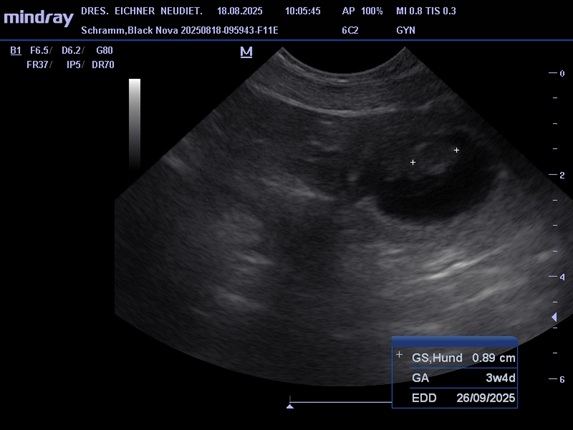

Unsere jüngsten Hündin Black Nova hatte ihr erstes Date mit Pepe am 19. 07. 2025. Pepe ist ein kräftiger kompakter Rüde mit sehr guten Gesundheitswerten. Die zwei haben sich beim Date und auch schon bei einem vorhergehenden Treffen gleich verstanden. Am 18.07. waren wir dann beim Ultraschall, das Ergebnis war positiv, somit erwarten wir Mitte September kleine Bullis in unseren Kennel. In der Nacht vom 20. zum 21. 09. 2025 sind 7 kleine Apfelknirpse bei uns gelandet, 4 Rüden und 3 Hündinnen. Nova und den Welpen geht es gut alle sind wohlauf. Alle Knirpse haben ihr Zuhause gefunden und sind ausgezogen.